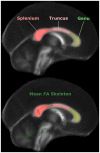

Methods: The biomarker question was addressed in this study by adopting a standardised protocol both for the whole brain (tract-based spatial statistics), and for a region of interest: the midline corpus callosum. In order to study the evolution of tensor changes, cross-sectional data from very mild (N = 21) and mild (N = 22) Alzheimer's disease patients were examined as well as a longitudinal cohort (N = 16) that had been rescanned at 12 months.

Findings and significance: The results revealed that increased axial and mean diffusivity are the first abnormalities to occur and that the first region to develop such significant differences was mesial parietal/splenial white matter; these metrics, however, remained relatively static with advancing disease indicating they are suitable as 'state-specific' markers. In contrast, increased radial diffusivity, and therefore decreased fractional anisotropy-though less detectable early-became increasingly abnormal with disease progression, and, in the splenium of the corpus callosum, correlated significantly with dementia severity; these metrics therefore appear 'stage-specific' and would be ideal for monitoring disease progression. In addition, the cross-sectional and longitudinal analyses showed that the progressive abnormalities in radial diffusivity and fractional anisotropy always occurred in areas that had first shown an increase in axial and mean diffusivity. Given that the former two metrics correlate with dementia severity, but the latter two did not, it would appear that increased axial diffusivity represents an upstream event that precedes neuronal loss.